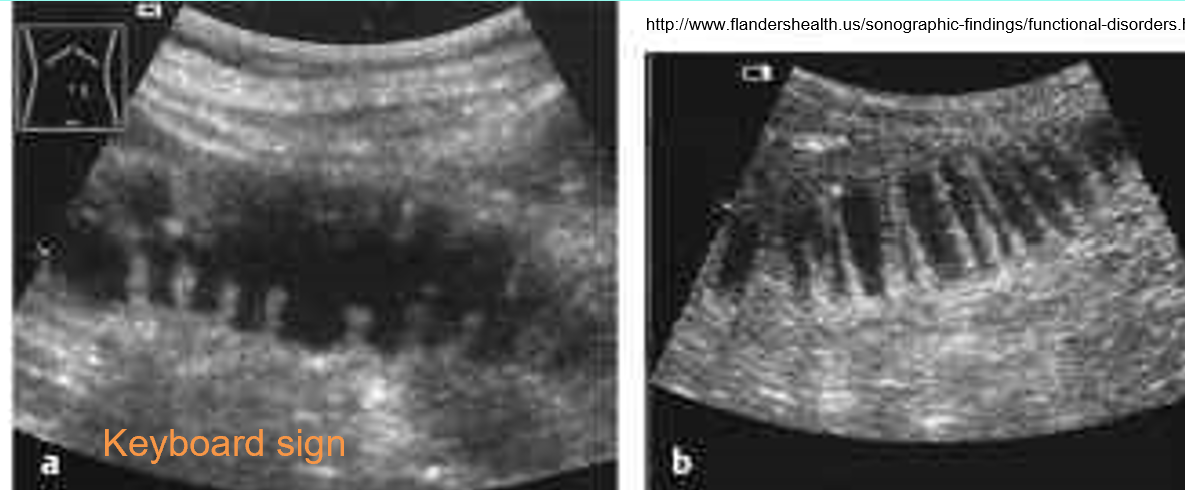

what is keyboard sign?

•valvulae conniventes seen as linear structures closely spaced along wall of duodenum & jejunum

what is shown?